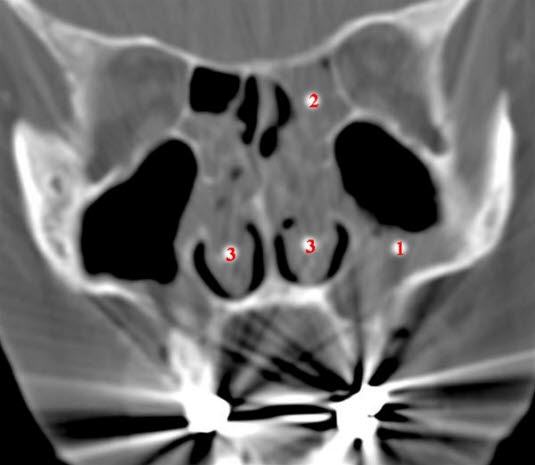

CT coronalbilde

Væske og sannsynlig basal slimhinnefortykkelse i begge maxillarsinus, mest uttalt på høyre side (1)

Utfylling av ethmoidalcellene (2)

Nesepolyppose (3)

Stripeartefakter fra tannfyllinger